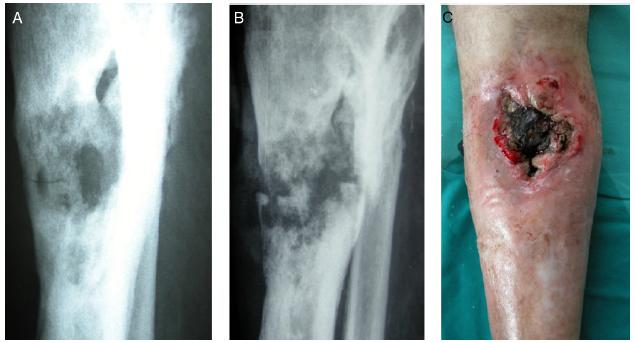

Osteomyelitis Là tình trạng nhiễm trùng ở xương, nhiễm trùng này đặc biệt phổ biến ở cột sống, trong bàn chân hoặc gót chân, hoặc cạnh khớp nhân tạo nếu khớp bị nhiễm trùng. Viêm xương tủy nhiễm khuẩn thường xảy ra sau một nhiễm trùng nghiêm trọng đã lan vào máu, đưa vi khuẩn vào trong xương. Viêm xương tủy của chân hoặc gót chân thường xảy ra do nhiễm trùng lây lan từ vết loét bàn chân.

Triệu chứng Osteomyelitis là Đau, sốt, chảy mủ qua da, loét da.

Chụp X-quang và chụp cộng hưởng từ (MRI) có thể phát hiện nhiễm trùng xương.

Điều trị Osteomyelitis dùng Kháng sinh đường tĩnh mạch, kháng sinh đường uống; phẫu thuật có thể cần thiết để loại bỏ các mô xương chết. Nếu khớp nhân tạo bị nhiễm trùng, các phần cứng có thể cần phải được loại bỏ. Nhiễm trùng xương đòi hỏi nhiều tuần điều trị kháng sinh tiêm tĩnh mạch (6 tuần hoặc lâu hơn) và thường đòi hỏi thời gian nằm viện dài.

Click vào ảnh để xem 5 hình ảnh minh họa